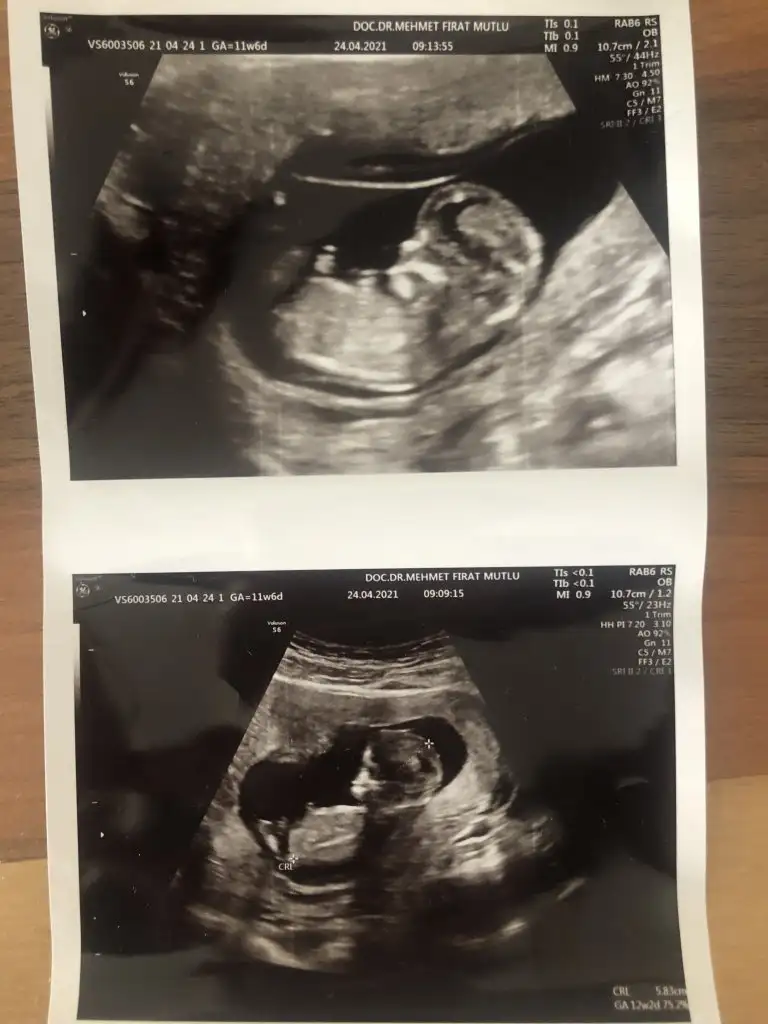

Canım Ikra meyra Ikra meyra bu ultrasona da bakar mısın cok merak ediyoruz bi yakınımızın😇 12.haftada

Eklentiler

• 0348DA3E-1526-4C95-845A-A221E6980DCA.webp

0348DA3E-1526-4C95-845A-A221E6980DCA.webp

19,2 KB · Görüntüleme: 60